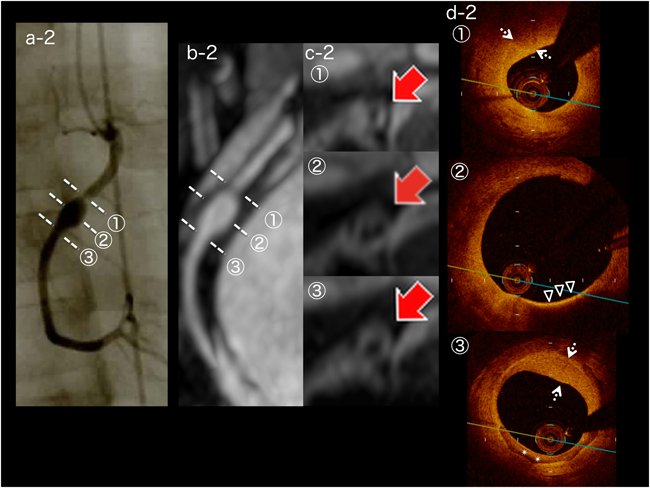

Fig. 2 Image findings for Case 2

On coronary angiography and magnetic resonance coronary angiography, the maximum diameter of the aneurysm (segment 2) is 5.4 mm, and the proximal part of the aneurysm shows localized stenosis (a-2, b-2). Vessel wall imaging shows thickening at all parts of the aneurysm (c-2, arrows). On optical coherence tomography imaging (d-2), intimal thickening with fibrosis (dashed arrows), a lipid-laden intima (open triangles), and calcified intima (asterisks) are evident.